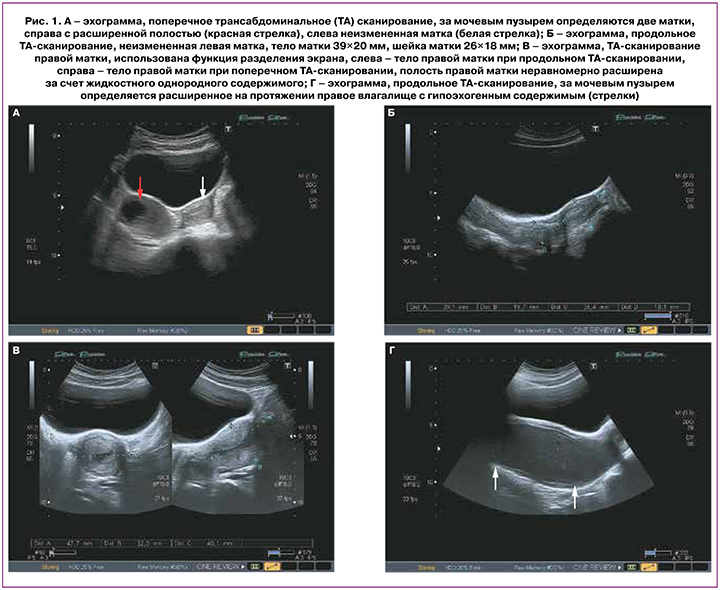

При ультразвуковом исследовании органов малого таза: матка удвоена (рис. 1А), тело правой матки 49×28×54 мм, шейка правой матки 21×31 мм, эхо-структура миометрия не изменена, полость матки расширена до 10 мм (рис. 1В), цервикальный канал расширен до 5 мм, верхняя и средняя треть влагалища расширены до 104×51×68 мм (рис. 1Г), содержимое неоднородное; тело левой матки 39×20 мм, шейка левой матки 26×18 мм, эхо-структура миометрия не изменена, полость матки не расширена (рис. 1Б).